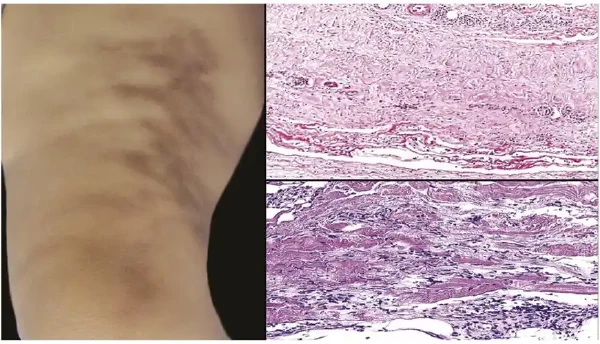

33岁的男性赵先生近期发现自己的大腿和臀部出现了多个皮下结节,伴随轻微疼痛和不适。经过在四川省人民医院皮肤科的诊断,赵先生被确诊为结节性脂膜炎。结节性脂膜炎是一种较为少见的炎症性疾病,主要累及皮下脂肪组织,往往会给患者带来极大的困扰和不适。

结节性脂膜炎的具体病因目前尚不完全明确,但一般认为是由多种因素共同作用导致的。这些因素可能包括感染、免疫反应、药物反应、物理刺激、代谢紊乱等。病理表现为皮下脂肪组织的炎性反应,导致脂肪细胞坏死和组织纤维化,从而形成一个个硬结。

通常,结节性脂膜炎最常见于女性,尤其是在20至60岁之间的中青年人群中较为多见。然而,随着生活方式的改变和环境因素的变化,男性患者数量也呈上升趋势。这种疾病最常发生在四肢的伸侧,比如大腿、胫骨、臀部等位置。结节初期颜色淡红,触感较硬,随着时间推移,可能会变得更加坚硬并伴随着疼痛。这种疾病虽然不至于致命,但会严重影响患者的生活质量,特别是若病情反复发作,更是让人难以忍受。